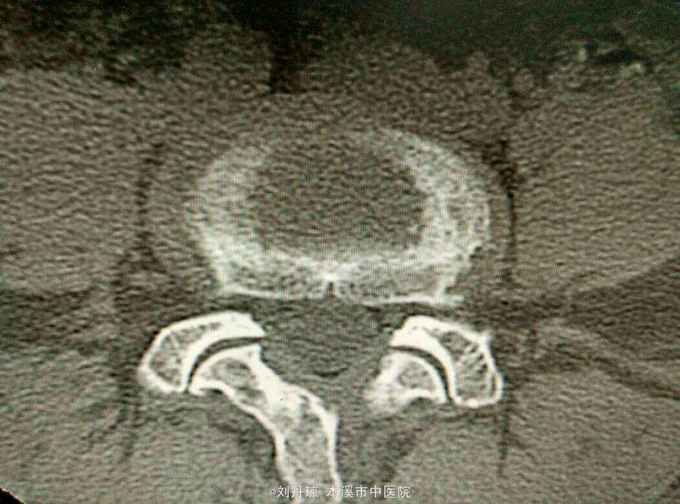

查体:L5—S1棘突旁压痛阳性。直腿抬高实验。左70度,右30度。加强试验左侧阴性,右侧阳性。腰椎功能障碍。CT:L5—S1椎间盘突出。